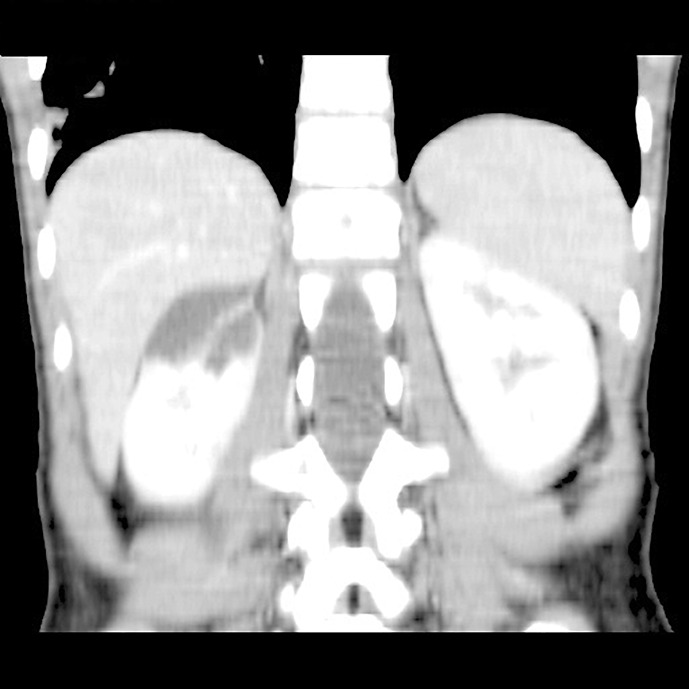

Case report: In a 6-year-old girl examined for abdominal pain, a cystic mass in the upper part of the right kidney was detected during an abdominal ultrasound. She was referred to pediatric oncology and urology for suspicion of a tumorous mass and the condition was assessed as a cystic nephroma. A heminephrectomy was then performed on the upper cystic part of the right kidney. The histological examination was inconclusive; therefore, genetic testing was recommended. Kidney and liver cysts were detected sonographically in the mother, but DNA analysis of the PKD1 and PKD2 genes did not reveal any pathogenic variant; the cause of the pathological formation in the kidneys remained unclear. Nine years later, next-generation sequencing of a panel of genes for kidney disease was performed and a heterozygous deletion was found on chromosome 16; this included exon 13 of the IFT140 gene. The same deletion was found in the patient's mother. Currently, the patient is 14 years old and has mild sonographic findings, normal glomerular filtration, mild proteinuria, and hypertension.